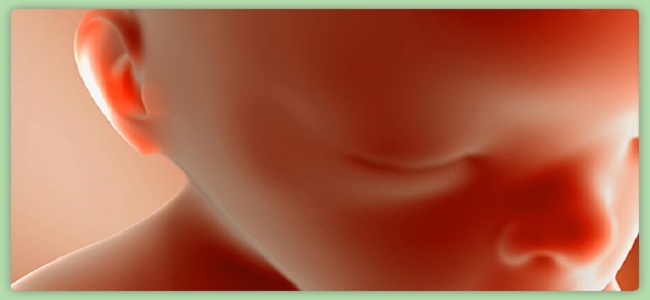

W 15 tygodniu ciąży ciało dziecka nabiera proporcji. Wydłużają się nóżki i rączki. Główka może pokryć się włosami. Nie jest to regułą, ponieważ dziecko równie dobrze może urodzić się łyse. Skóra malucha jest nadal przezroczysta i widać przez nią sieć naczyń krwionośnych. Dziecko ma już 11 cm i waży około 40 gramów.